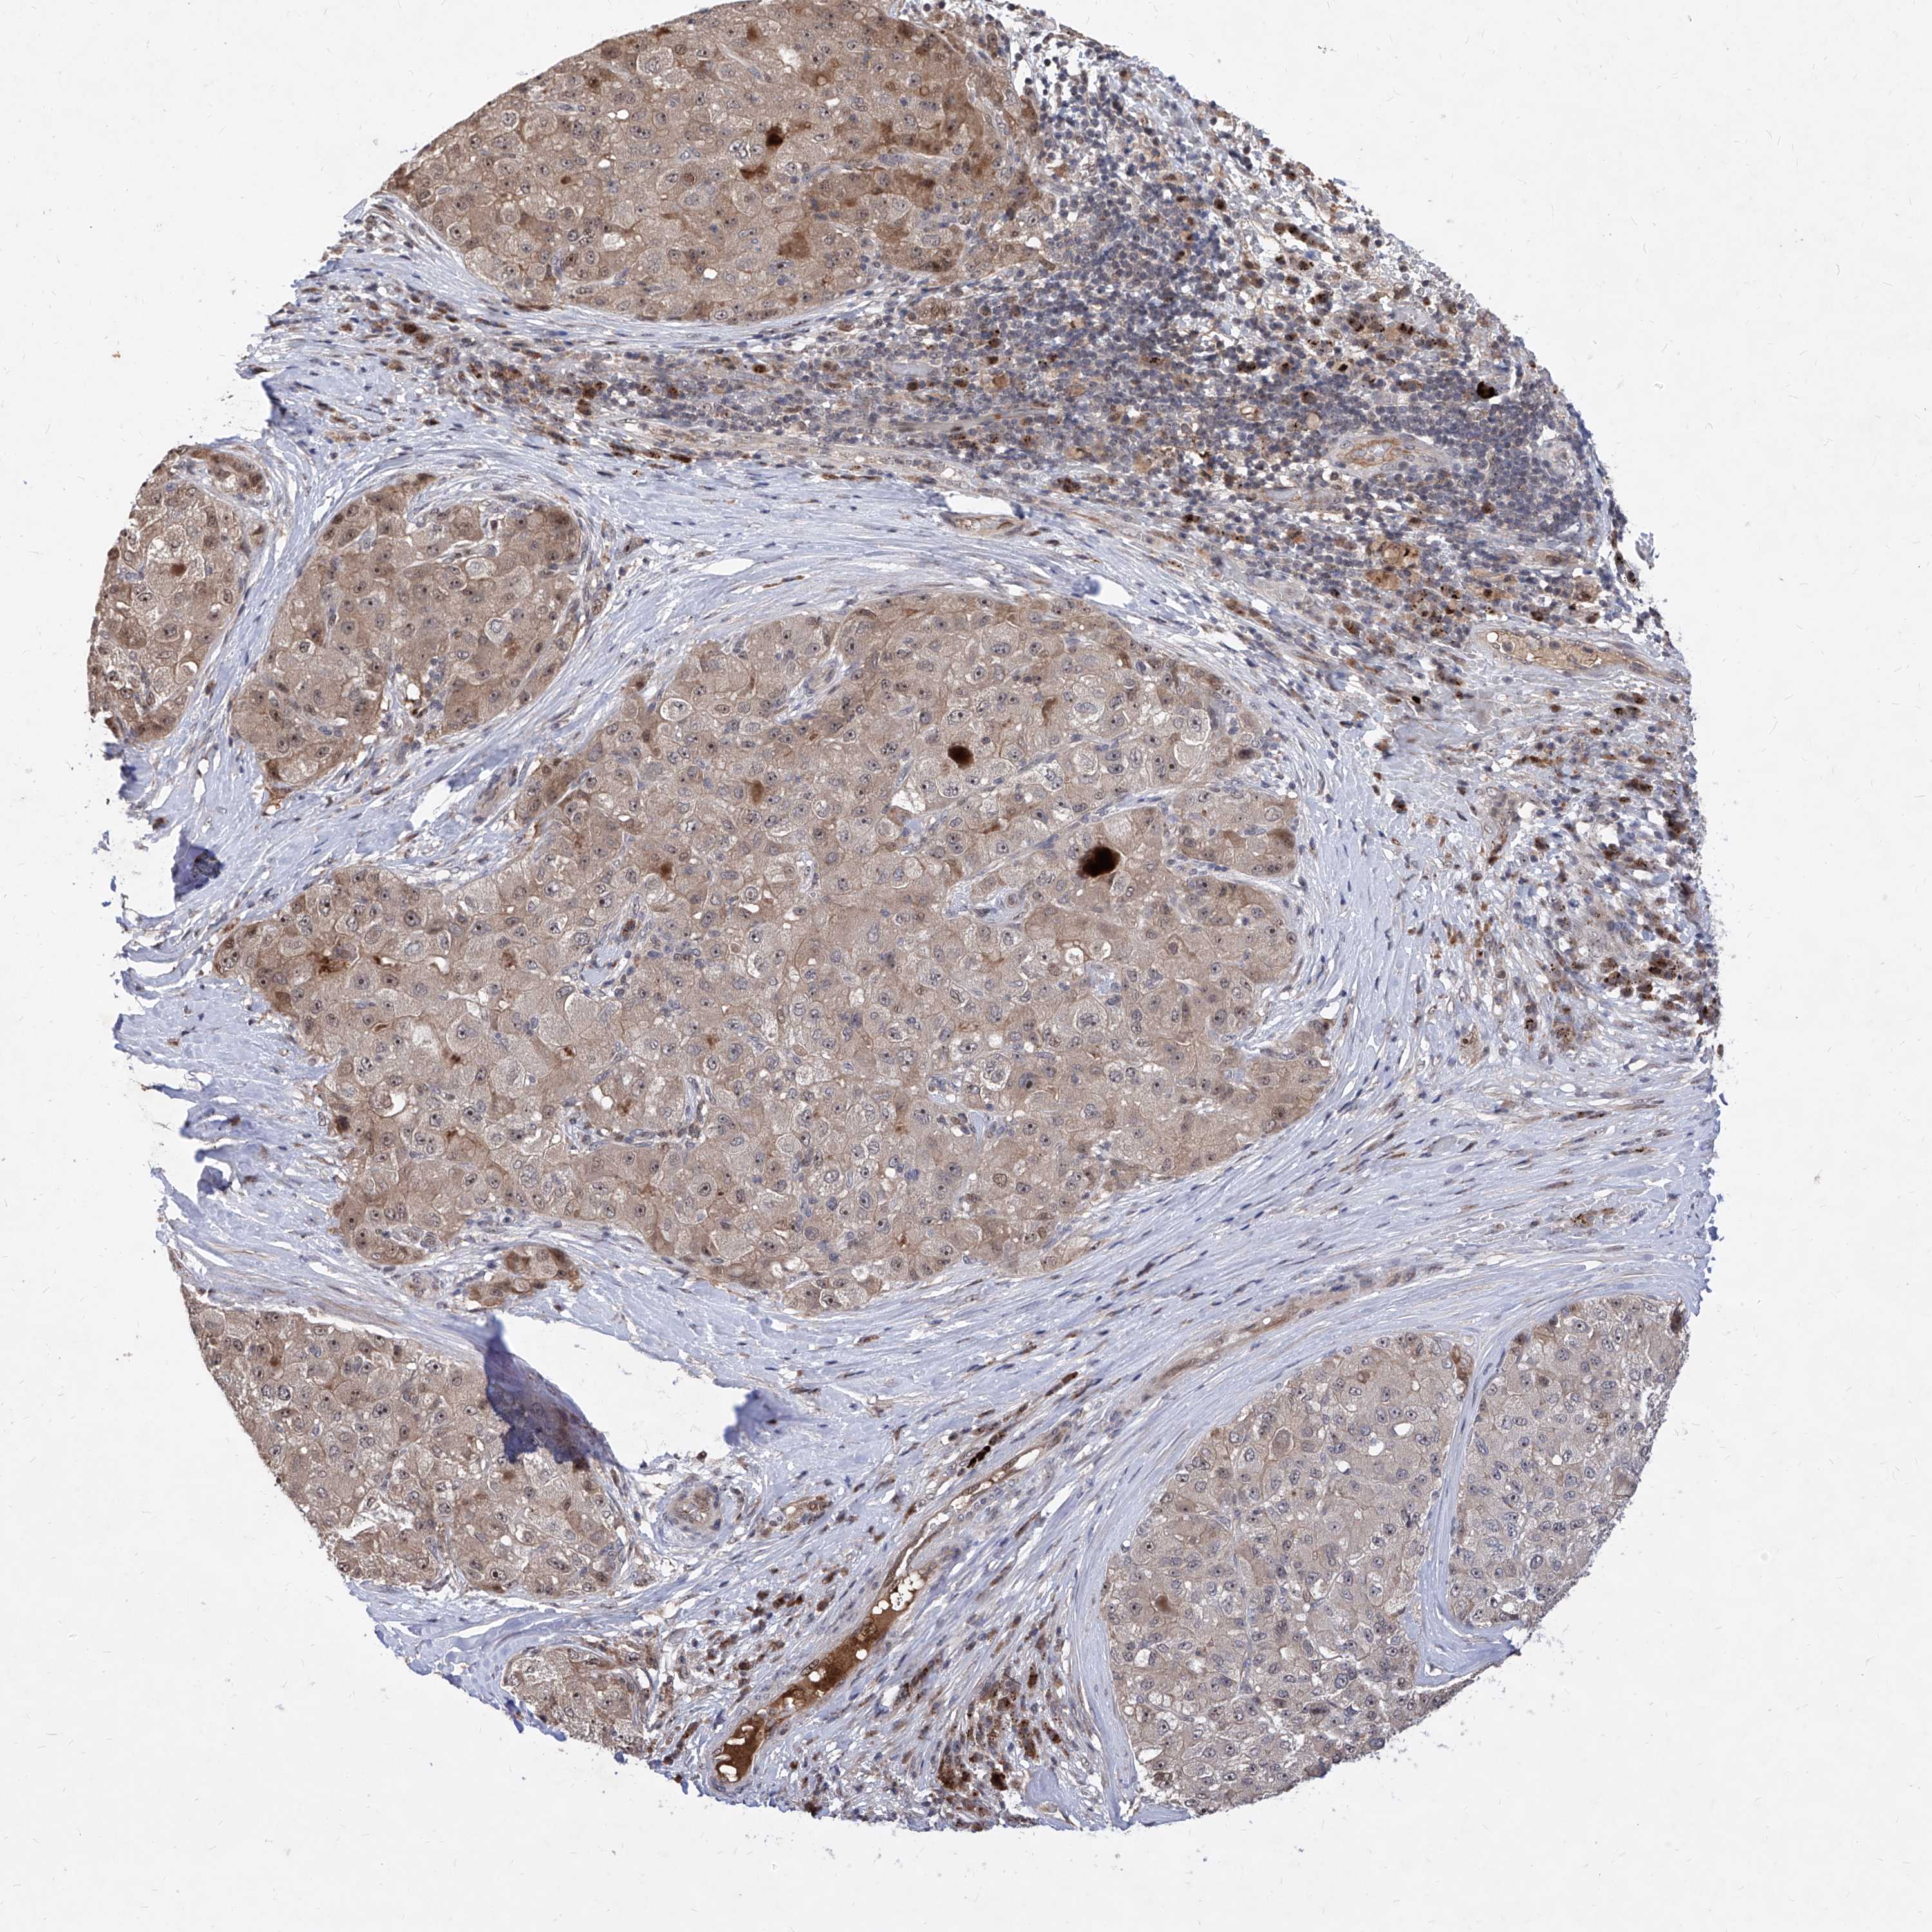

LIVER CANCER - Protein expressioni

A mouse-over function shows sample information and annotation data. Click on an image to view it in a full screen mode. Samples can be filtered based on level of antibody staining by selecting one or several of the following categories: high, medium, low and not detected. The assay and annotation is described here.

Note that samples used for immunohistochemistry by the Human Protein Atlas do not correspond to samples in the TCGA dataset.

Antibody stainingi

Antibody staining in the annotated cell types in the current human tissue is reported as not detected, low, medium, or high, based on conventional immunohistochemistry profiling in selected tissues. This score is based on the combination of the staining intensity and fraction of stained cells.

Each image is clickable and will lead to virtual microscopy that enables deeper exploration of all samples and also displays staining intensity scores, fraction scores and subcellular localization as well as patient and tissue information for each sample.

Antibody HPA030267

Staining

High

Medium

Low

Not detected

Intensity

Strong

Moderate

Weak

Negative

Quantity

>75%

75%-25%

<25%

None

Location

Nuclear

Cytoplasmic/membranous

Cytoplasmic/membranous,nuclear

Cholangiocarcinoma

Carcinoma, Hepatocellular, NOS